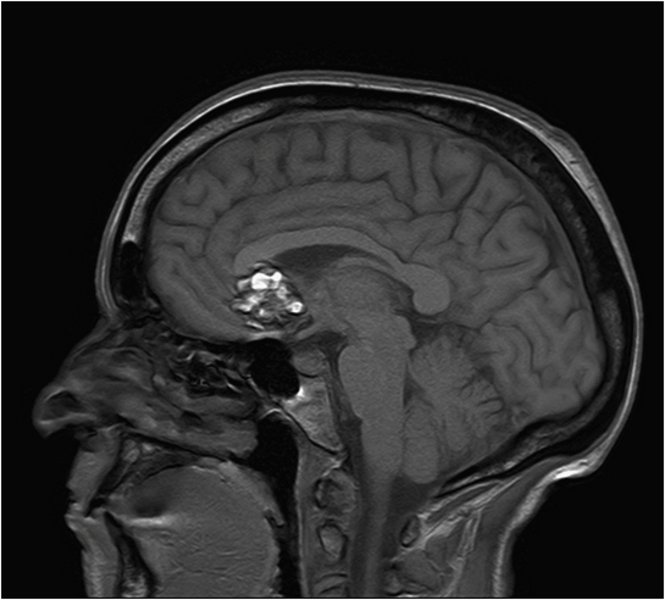

Kavernom - T1 sagittal

Charkateristische Haemosiderinabbauprodukte in Form

von hypointensen Signalalterationen